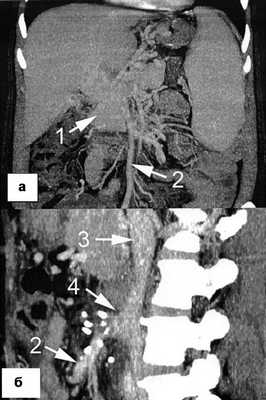

Больная Р., 49 лет, госпитализирована в Государственную новосибирскую областную клиническую больницу в связи с выявленным асимптомным варикозным расширением вен пищевода. За год до поступления при скрининговом ультразвуковом исследовании было обнаружено гиперваскулярное образование в области ворот печени, а при последующей компьютерной томографии в другом стационаре в области ворот печени визуализировано мягкотканное образование с нечеткими контурами размером 5×5×4 см (рис. 1, а), Рисунок 1. Спиральная компьютерная томограмма до (а) и после (б) мезентерико-кавального шунтирования. 1 - портальная кавернома, первоначально принятая за опухоль ворот печени; 2 - верхняя брыжеечная вена; 3 - нижняя полая вена, 4 - мезентерико-кавальный анастомоз. расцененное как опухоль ворот печени. При этом больная не предъявляла каких-либо жалоб, не было изменений в биохимическом анализе крови, гемограмме и отсутствовали характерные для опухолей данной локализации проявления механической желтухи. Месяцем позже в другом лечебном учреждении была выполнена лапароскопия, во время которой не найдено признаков неопластического процесса в брюшной полости, но обращено внимание на наличие спленомегалии и множества расширенных вен в области малого сальника и брыжейки тонкой кишки. Тогда же была произведена биопсия печени, а после гистологического исследования получено заключение о формирующемся микронодулярном циррозе. В течение 11 мес пациентка наблюдалась и лечилась в различных гастроэнтерологических отделениях с диагнозом криптогенного цирроза печени, во время последней госпитализации эндоскопически было выявлено варикозное расширение вен пищевода.

1) веногепатография - контрастное вещество, введенное посредством заклиненного в печеночной вене катетера, хорошо проходит через синусоидальное русло, что исключает синусоидальный блок портального кровотока (рис. 3); Рисунок 3. Веногепатограмма (а) и мезентерикопортограмма (б) перед операцией. 1 - верхняя брыжеечная вена; 2 - кавернозная трансформация воротной вены; 3 - варикозное расширение вен пищевода.

2) мезентерикопортография - визуализирована верхняя брыжеечная вена диаметром 8 мм, проходимая до места слияния с селезеночной веной, воротная вена кавернозно трансформирована, сброс контрастного вещества через вены пищевода (рис. 3, б);

3) компьютерная томография - визуализированы описанные ранее изменения в области печеночно-двенадцатиперстной связки и ворот печени, верхняя брыжеечная вена проходима, воротная и селезеночная вены тромбированы (см. рис. 1, а).

При эзофагогастродуоденоскопии перед выпиской отмечена хорошая редукция варикозно-расширенных вен пищевода (рис. 2, б), при компьютерной томографии через 1 мес после выписки визуализирован проходимый мезентерико-кавальный анастомоз (рис. 1, б). Во время контрольного осмотра через 3 мес состояние пациентки удовлетворительное, принимает кардиомагнил по 75 мг/сут, доза гидроксикарбамида снижена до 1000 мг/сут. Показатели гемограммы: Hb 107 г/л, эр. 5,04·10 12 /л, л. 9,6·10 9 /л, Ht 32,9%, тр. 505·10 9 /л, средний объем эритроцитов 65 фл, среднее содержание гемоглобина в эритроците 21,3 пг, лейкоцитарная формула не изменена.